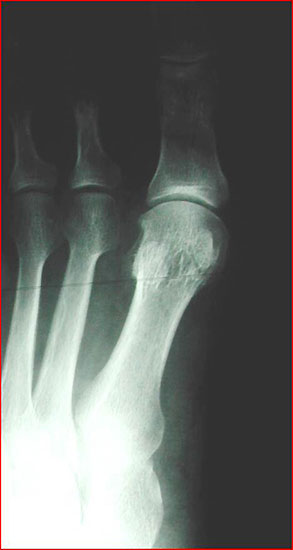

Wenn durch das Anspannen der Muskulatur der 1. Strahl zu einem starren Hebel wird und aussteift, empfehlen wir auf die Durchführung einer TMT-I-Arthrodese zu verzichten und z.B. eine proximale Korrekturosteotomie durchzuführen. So ist nach unserer Auffassung bei jeglicher Dorsalbewegung des 1. Strahles (Instabilität) trotz Anspannung der Peronealmuskulatur (wie beschrieben) die Indikation zur Lapidusarthrodese unabhängig vom Intermetatarsalwinkel gegeben. Bei der Beurteilung des a.p.-Röntgenbildes unter Belastungsbedingungen dient die Bestimmung des Hallux valgus interphalangeus-Winkes und des distalen Artikulationswinkels ggf. zur Indizierung einer additiven Akin-Osteotomie (Abb. 4). Die Stellung des proximalen Artikulationswinkels legt im Falle einer bereits praeoperativ bestehenden Vergrößerung nach Korrektur des Intermetatarsalwinkels eine Korrektur durch eine Reverdin-Green-Laird-Osteotomie nahe (Abb. 5). Die Größe des Intermetatarsalwinkels I/II beeinflusst je nach Größe bei stabilem 1. Strahl die Wahl des jeweiligen Operationsverfahrens.

Im Falle einer Insuffizienz des 1. Strahles wird in jedem Falle eine TMT-I-Arthrodese indiziert sein, hier dient der Intermetatarsalwinkel planerischen Aspekten im Sinne des Ausmaßes der Korrektur am Os cuneiforme I. Die Bestimmung des Metatarsus adductus-Winkels dient der Detektion eines Pes adductus. Im Falle des Vorliegens einer solchen Deformität sind ggf. auch Korrekturosteotomien an den kleineren Metatarsalia zu erwägen, um ausreichend Platz für die Einstellung des Metatarsale I in die Rectusposition zu erhalten. Ein weiteres wichtiges Kriterium in der a.p.-Projektion stellt das Längenverhältnis von Metatarsale I zu Metatarsale II dar, da bei der Durchführung der TMT-I-Arthrodese das Vorliegen einer Minusvariante häufiger die Gefahr einer postoperativen Transfermetatarsalgie birgt und hier unter Umständen über Modifikationen des operativen Vorgehens nachgedacht werden sollte. Hier besteht die Möglichkeit von alternativen Präparationsverfahren im TMT I oder aber der Durchführung einer Interpositionsarthrodese des TMT I zur Verlängerung des 1. Strahles. Alternativ können auch Verkürzungsosteotomien des 2. und 3. Strahles erwogen werden. Als indirekte radiologische Zeichen einer Insuffizienz des 1. Strahles kann ein Klaffen des Spaltes zwischen dem Os cuneiforme mediale und dem Os cuneiforme intermedium sowie eine Hypertrophie der Corticalaes des Metatarsale II gedeutet werden (Abb. 6).